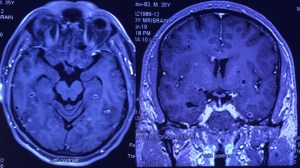

Disseminated cysticercosis (tapeworm)in a vegetarian male

Disseminated cysticercosis (tapeworm) in a vegetarian male

Prahlad K Sethi, MD and Nitin K Sethi, MD,

A 35-year-old vegetarian man presented with a generalized convulsion. MRI brain showed extensive cysticerci lesions involving the bilateral supra and infra-tentorial brain parenchyma, myofascial planes of the face, neck, floor of mouth, parotid glands and left orbital extraocular muscles (figure 1). MRI thigh showed diffuse cysticerci involving multiple muscles (figure 2). Disseminated cysticercosis can occur in vegetarians and non-pork eaters due to fecal-oral contamination of food with Taenia solium eggs from tapeworm carriers1.